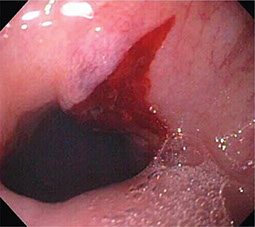

Desgarro de Mallory-Weiss

Se refiere a laceraciones en la membrana mucosa del esófago, normalmente causados por hacer fuertes y prolongados esfuerzos para vomitar o toser.

El diagnóstico y tratamiento se realiza con una endoscopia, para suturar o ligar una arteria sangrante.